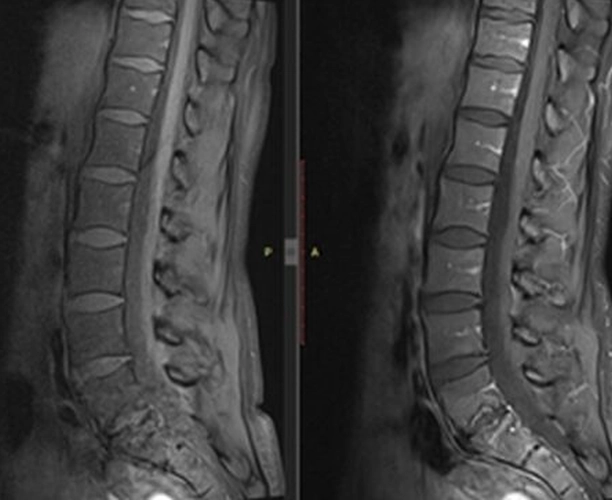

Resim 1: Lomber MRG T2 Sagittal

Laboratuvar: AFR normal. Rutin biyokimya normal. Brucella negatif. HLA-B27 negatif. Görüntüleme: Sakroiliyak MR olağan. Mevcut lomber MR’da L5–S1 düzeyinde spondilodiskit açısından şüpheli görünüm izlenmesi üzerine kontrastlı lomber MR istendi.

Ayırıcı tanı (Modic Tip 1 dejenerasyon? Spondilodiskit?) için sintigrafi önerildi. NSAİİ ve hareket kısıtlaması önerildi.

Kemik sintigrafisi görüldükten sonra spondilodiskit olasılığı elendi. L5-S1'deki disk lezyonu geçirilmiş bir travma ya da Schmorl nodülüne sekonder olarak artmış yoğun dejeneratif değişiklikler olarak değerlendirildi. 1600 mg/gün NSAİİ tedavisi ile kısmi fayda görüldü. Ağrı sadece sol değil sağ kasık bölgesine de ara ara yayılım gösteriyor artık ancak şiddet daha azdı. Hastaya fizyoterapi, günlük yaşam aktivitelerinde dikkat etmesi gerekenler ve kısıtlamalar önerildi ve takip planlandı.